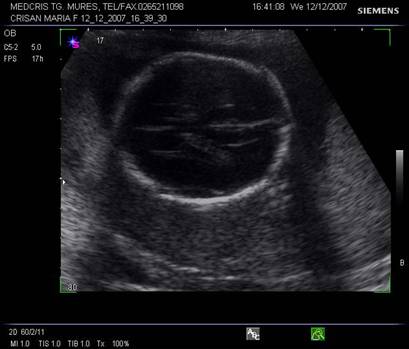

Planul III sau planul frontooccipital, pentru masurarea diametrelor biparietal si frontoocipital. Ecoul de mijloc frontoocipital este intrerupt in zona cavum septum pellucidi, anecogena, situata anterior de ventriculul III. Acesta este situat intre doi nuclei talamici hipoecogeni si apare ca o despicatura mica sau o linie.

Fig. nr. 151 Planul III de sectiune transversala a craniului fetal.